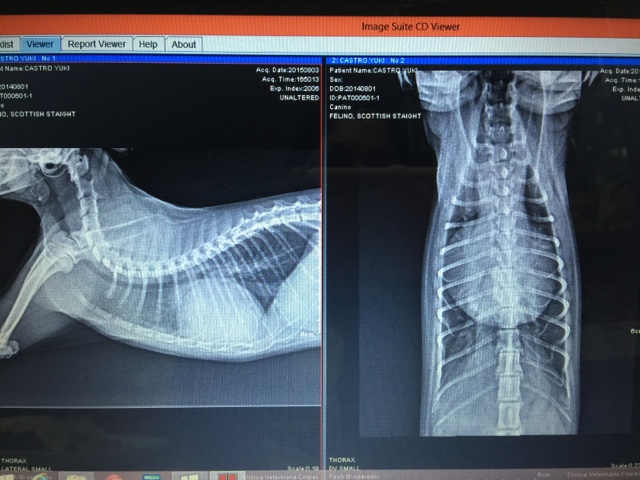

Inmediatamente nos dirigimos al mejor cardiólogo de mi ciudad y después de evaluarlo, revisar los anteriores resultados, sacarle una placa y ecocardiograma, concluyó con el siguiente diagnóstico que a continuación detallo:

Mi Yuki ... Cardiomiopatía hipertrófica severa con dilatación biatrial severa y éstasis sanguíneo secundario. Fibrosis subendocárdica.

Rayos X